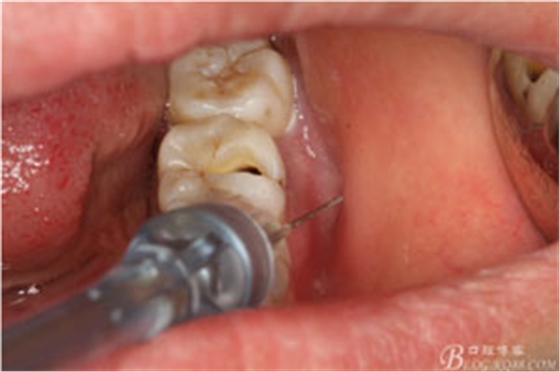

圖2.37牙冠基本完好,松動Ⅰ度。合面有一開髓孔被棉球覆蓋,頰側(cè)牙齦輕度紅腫。

圖3.取出棉球口內(nèi)發(fā)現(xiàn)37合面有開髓孔,探針出血,頰側(cè)牙齦紅腫